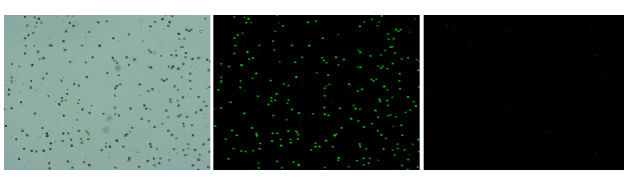

肝臟是人體代謝和解讀的器官,在體內發揮氧化、儲存肝糖、合成分泌性蛋白合成等,肝臟也制造消化系統中之膽汁,人肝約有25億個肝細胞。但是解離肝臟組織懸液并不簡單,首先,肝臟代謝旺盛,離體后肝細胞無法進行正常的有氧糖酵解,細胞活力會迅速下降,另外,肝細胞的線粒體很多,每個細胞大約有1000個左右,遍布于胞質內。因此,很難得到符合單細胞測序要求的單細胞懸液。百邁客生物在肝臟組織單細胞懸液制備方面有豐度的實操經驗,開發了獨有的解離體系,下面來看實驗結果:

實驗結果

人肝癌樣本,懸液背景干凈,活性91.69%,結團率6%

Tips: 肝實質細胞經過解離后因為缺氧非常容易發生凋亡,導致占比很低,如果老師關注肝實質細胞的話,建議采用單細胞核懸液的方法。